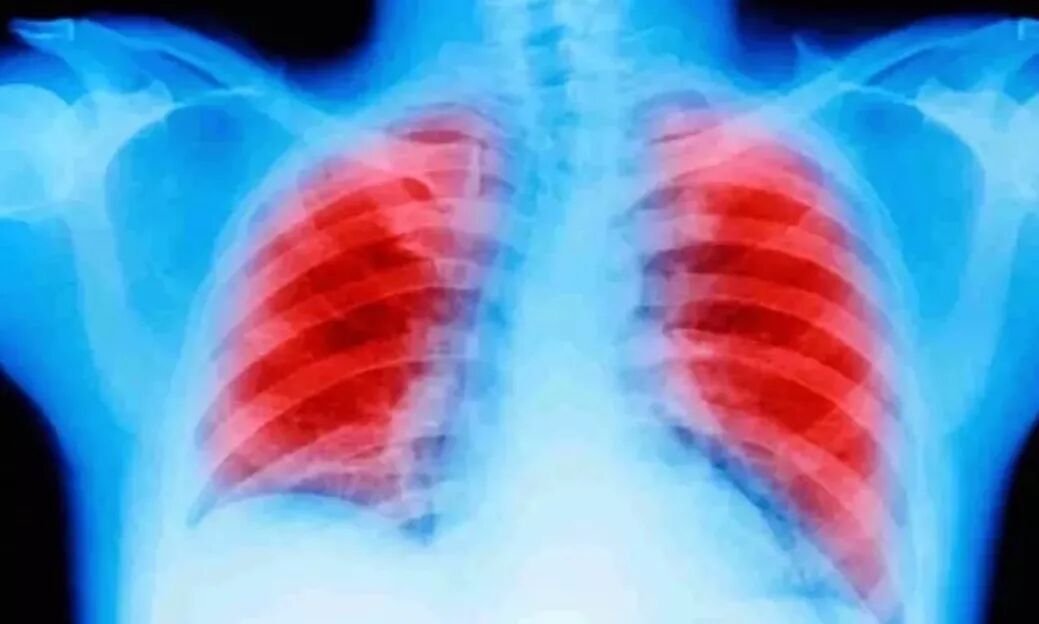

目前,手术、化疗和放疗是治疗肿瘤的三大常规方法,但它们都给癌症病患带来极大的痛苦。近年,被称为“绿色新疗法”的第四种方法——细胞免疫疗法出现,并逐渐应用于临床。相较于传统疗法,免疫治疗具备反应快、效果明显、副作用小的核心对比优势。

所谓免疫治疗,是指在治疗过程中直接或者间接利用人体免疫细胞对肿瘤患者进行有效治疗的方法。这一继手术、放疗和化疗之后的肿瘤新疗法,被誉为唯一有可能完全消除癌细胞的治疗方法。 免疫疗法:即将到来的第三次抗肿瘤革命!据最新的研究报道,免疫治疗将成为未来肿瘤治疗的主要手段,结合当前常用手术、化疗及放疗方法,为最大限度延长肿瘤患者生命甚至完全治愈提供了无限可能。

据统计,截止至2019年6月,目前FDA已经批准免疫治疗治疗近20种癌种,其中包括肺癌、肝癌、胃癌、黑色素瘤、乳腺癌、宫颈癌、白血病等多种肿瘤:

新浪网:好消息!免疫疗法在治疗肺癌方面取得了巨大的进步

来自约翰霍普金斯大学的Bloomberg-Kimmel癌症免疫治疗研究所和Sidney Kimmel癌症中心,以及Memorial Sloan-Kettering癌症中心的研究者团队,专门针对那些准备接受手术的20位早期肺癌患者,在手术前用免疫治疗药物预先治疗。实验结果显示:一年后,18名肺癌患者仍然活着。其中16名患者检测不到癌症。